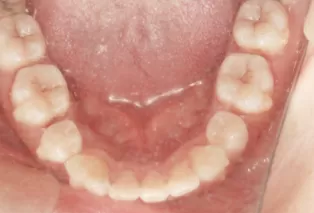

Photos intra-orales